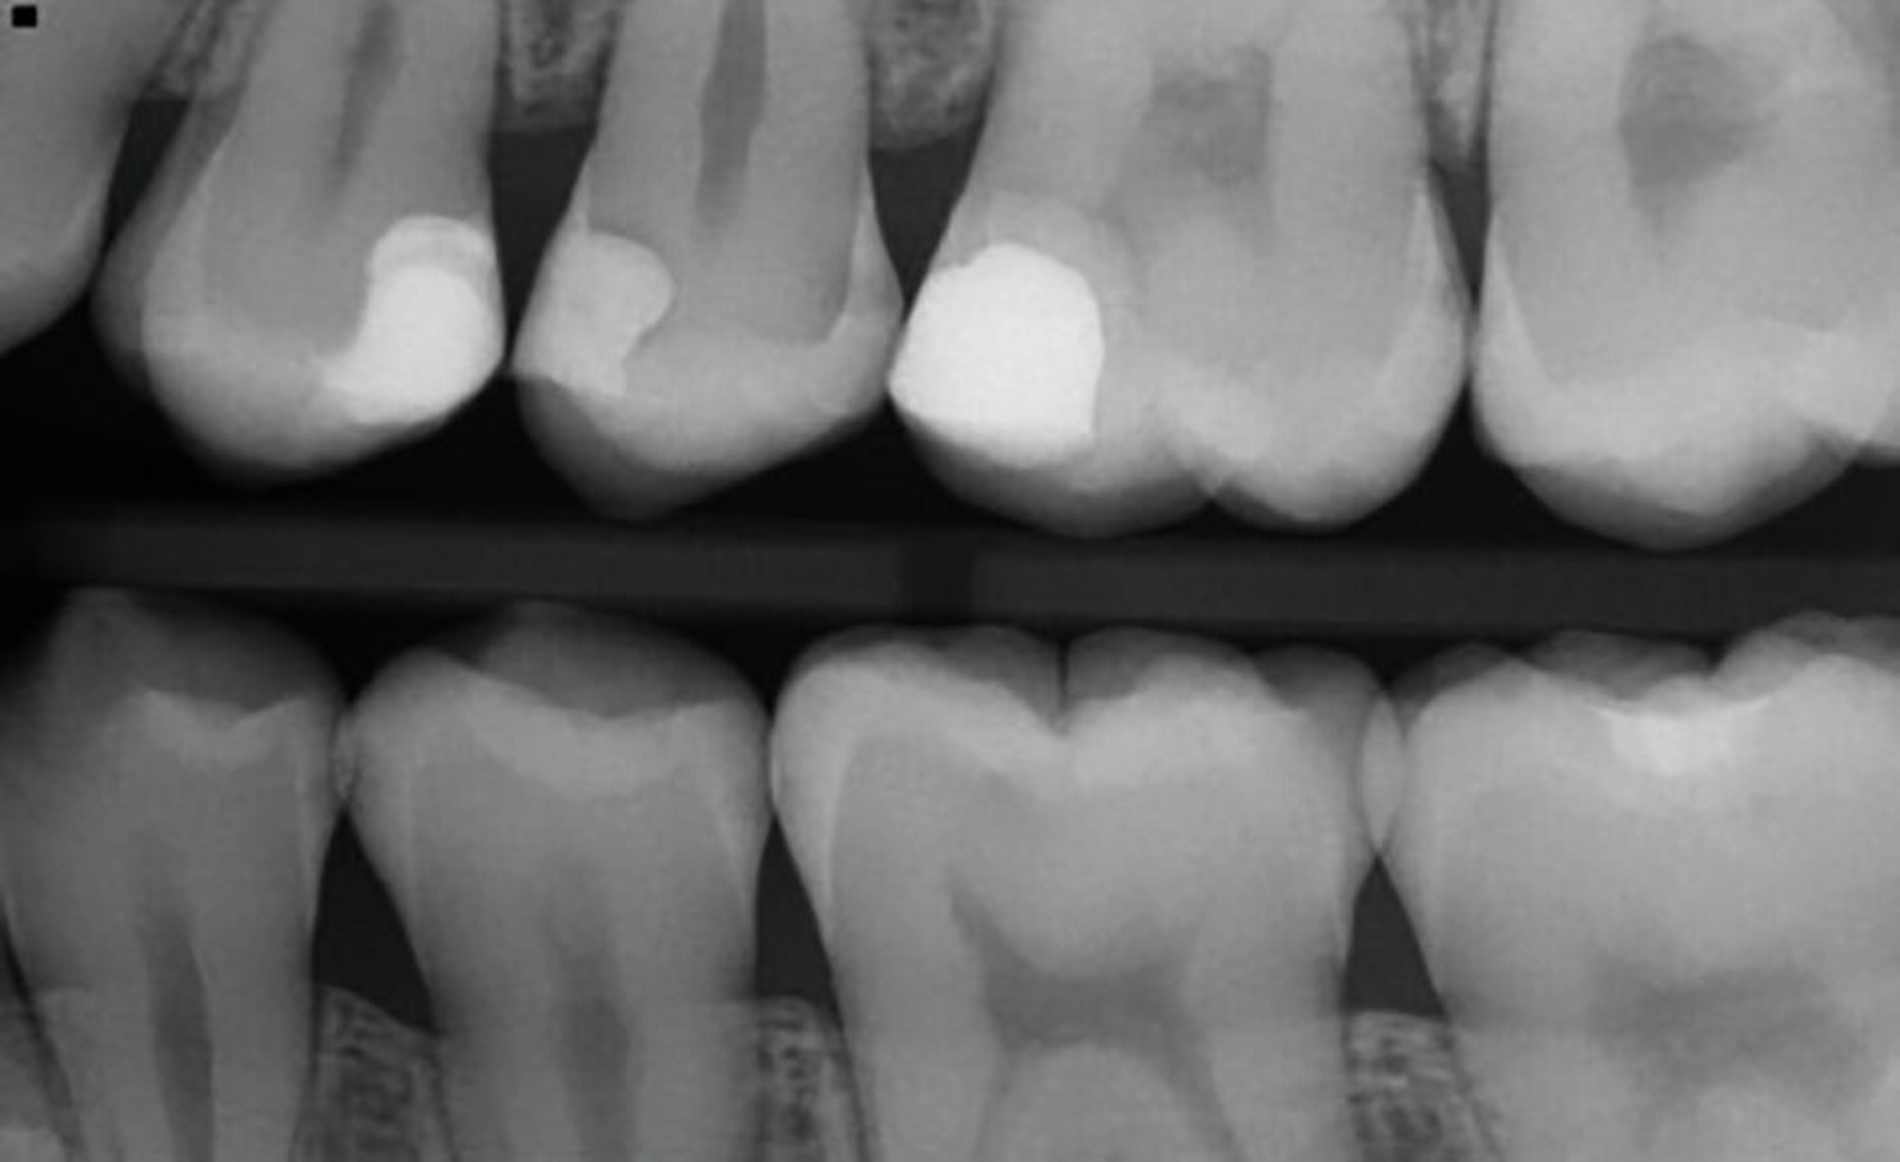

SDF eignet sich auch für die Behandlung von approximalen Läsionen. Besonders interessant wird die Anwendung von Silberfluoriden zur Behandlung von Initialkaries beziehungsweise nicht-kavitierter Karies im kariesaktiven permanenten Gebiss Jugendlicher (Abbildung 8).

Der verkürzt dargestellte Patientenfall zeigt dieses minimalinvasive, innovative und kostengünstige Behandlungskonzept [Ahmed et al., 2023]. Im Kern werden dazu nach vorheriger Diagnostik orthodontische Separiergummis in die Zahnzwischenräume eingesetzt und für circa ein bis zwei Stunden in situ belassen. Direkt nach der Entfernung der Gummis erfolgt eine zügige, direkte klinische Untersuchung der Approximalkaries und eine Applikation von SDF zur Kariesinaktivierung mittels Microbrush.

Der Patientenfall belegt röntgenologisch die hohe Kariesaktivität vor der Behandlung, sowie die deutlich reduzierte Kariesaktivität nach der einmaligen SDF-Applikation in der oben genannten Technik nach knapp eineinhalb Jahren anhand von Bissflügelaufnahmen (Abbildungen 8a bis 8g). Eine retrospektive Pilot-Untersuchung an der Kinderzahnheilkunde in Greifswald gibt deutliche Hinweise auf die Wirksamkeit dieser Technik. Die Ergebnisse wurden beim diesjährigen Weltkarieskongress vorgestellt und diese Studie wurde ebenfalls von ORCA prämiert. Die Ergebnisse dieses Pilotprojekts zeigen für gut 90 Prozent der behandelten E1/E2/D1-Läsionen über einem Zeitraum von 15 Monaten keine weitere Progression in den Bissflügelaufnahmen [Ahmed et al., 2024].